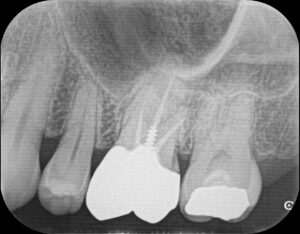

CTレントゲン検査を行いますのでその際、11000円かかります。

三か月後に経過のレントゲンを撮影し、最終補綴物を作製するか治りが悪い場合は外科処置(歯根端切除術)の案内になります。